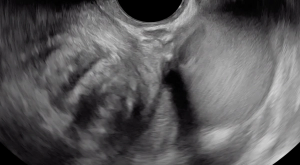

Viewers should focus their eyes on the area closest to the probe, the vagina. The hypoechoic area that is immediately abutting the probe is consistent in thickness and echogenicity throughout the sweep from right to left. There is other deep endometriosis in this clip (bowel and uterosacral ligament) and an ovarian endometrioma.

In transverse, this clip shows the right and left ovary both contain an endometrioma and the ovaries are fixed to each other medially, known as “kissing ovaries.” They are densely adherent to an area that also contains bowel deep endometriosis.